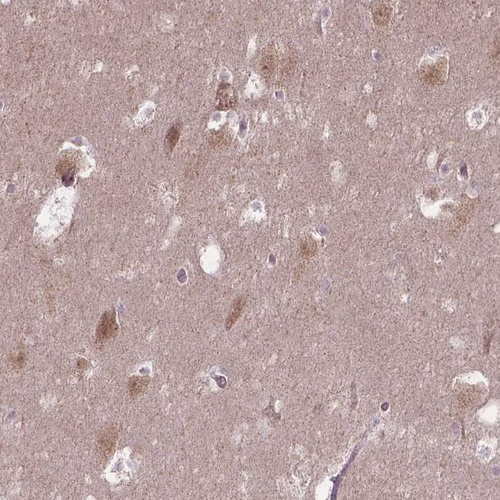

Immunohistochemical staining of human hippocampus shows moderate nucleolar positivity in neuronal cells.